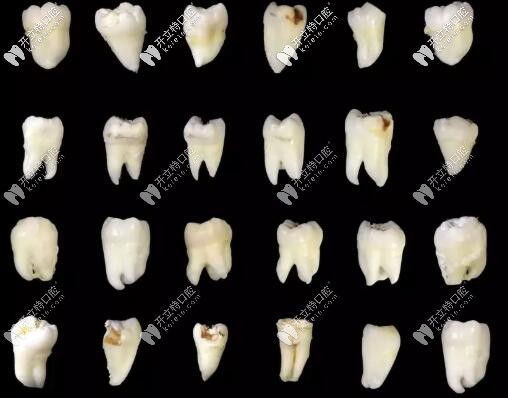

智齒的各種形態(tài)

這是某位醫(yī)生拔過的智齒

一般情況下,拔除一顆智齒的價(jià)格介乎于幾百元到幾千元之間,當(dāng)然不同的醫(yī)生級(jí)別,不同醫(yī)院也是收費(fèi)不一樣的,下面這個(gè)圖可以簡單對(duì)價(jià)格做一個(gè)衡量,僅供參考。